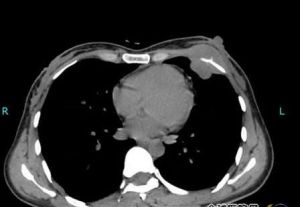

硬纖維瘤CT片硬纖維瘤表現為一生長緩慢的腫瘤,其症狀與腫瘤所在的部位有關。在家族性腺瘤性息肉病中,患者的性別、年齡以及腫瘤的部位與其他硬纖維瘤患者不同,其男女發病率幾乎相等,約80%~90%的腫瘤位於小腸系膜和腹壁,年齡多數為25-30歲。

2、CT影像學表現缺乏特異性。儘管硬纖維瘤具有局部侵襲性,但大部分在CT上表現為邊界清楚的軟組織腫塊,不見鈣化和囊變,與典型的呈浸潤生長的惡性腫瘤不同,結合臨床表現可加以區分。但有少部分邊界不清,呈浸潤狀。增強掃描時,與正常肌肉相比較大多為等密度或為高密度,少數為低密度。大部分為均勻強化,約1/3患者為中央低、邊緣高的環狀或條紋狀增強。